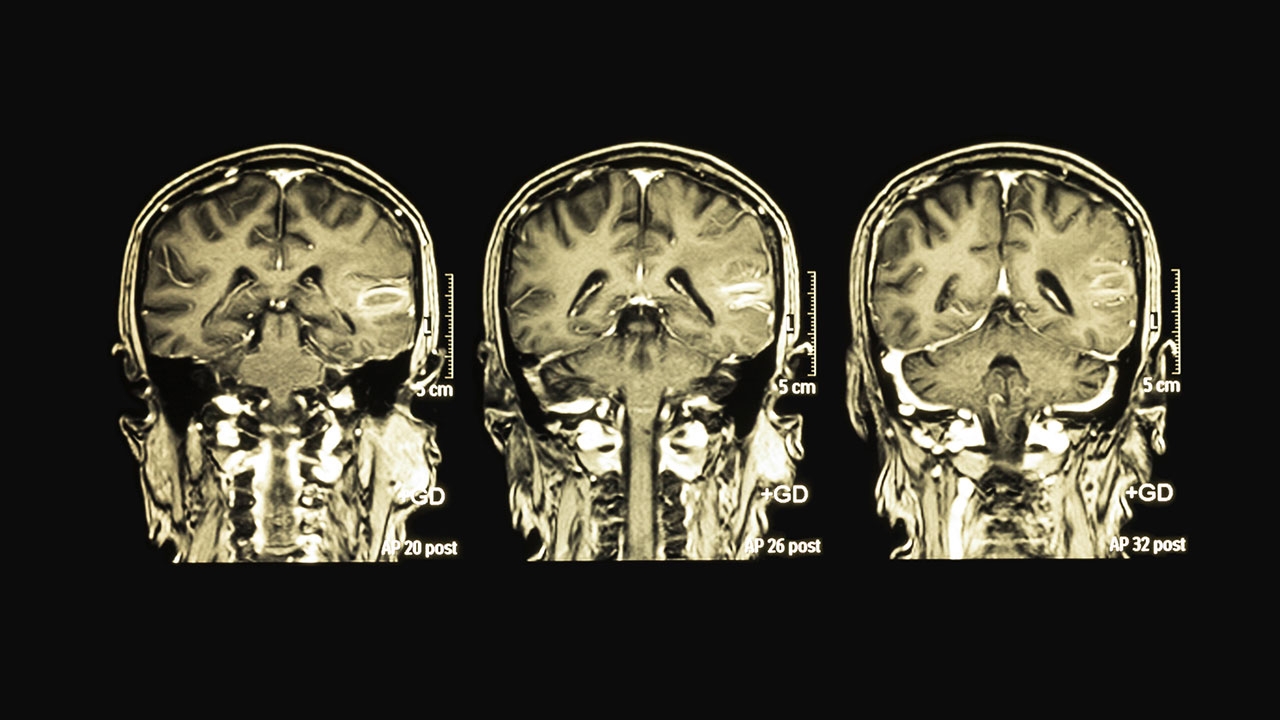

พญ.ไพรัตน์ แสงดิษฐ ผอ.สถาบันประสาทวิทยา กล่าวว่า สมองฝ่อ คือ ภาวะที่ปริมาณเนื้อสมองลดลง เป็นการเสื่อมของอวัยวะในร่างกายตามธรรมชาติ แต่เกิดกับสมองและมักเกิดขึ้นกับผู้สูงอายุวัย 75 ปีขึ้นไป โดยมีปัจจัยสำคัญที่เป็นสาเหตุ เช่น การเสื่อมของสมองตามวัย เกิดอุบัติเหตุที่ศีรษะกระทบกระเทือนสมอง การทานยาบางชนิด โรคประจำตัวบางชนิด เช่น การขาดวิตามินบี 12 โรคติดเชื้อในสมอง โรคหลอดเลือดสมอง และพฤติกรรมการใช้ชีวิตประจำวันที่ไม่เป็นประโยชน์ต่อสมอง เช่น ภาวะความเครียด พักผ่อนน้อย เป็นต้น โดยผู้ป่วยจะมีอาการดังนี้ ลืมสิ่งที่เพิ่งจะเกิดขึ้น ความสามารถในการช่วยเหลือตัวเองลดลง ความจำเสื่อม หลงลืม มีพฤติกรรมที่เปลี่ยนไป สำหรับการรักษาโรคสมองฝ่อ หากพบสาเหตุที่แก้ไขได้จะให้การรักษาตามสาเหตุและให้การรักษาตามอาการ ควรหลีกเลี่ยงรับประทานยาที่มีผลต่อการทำงานของสมอง ควรปรับสภาพแวดล้อมให้เอื้ออำนวยกับการประกอบกิจวัตรประจำวันของผู้ป่วย ให้ผู้ป่วยกินอาหารครบ 5 หมู่ ออกกำลังกายสม่ำเสมอ ส่วนการป้องกันการเกิดโรคสมองฝ่อ สามารถป้องกันได้หากปรับพฤติกรรมให้เป็นประโยชน์ต่อสมอง อาทิ ฝึกคิด การเล่นหมากรุก ฝึกคิดเลข รับประทานอาหารที่มีประโยชน์ ไม่ดื่มสุรา งดสูบบุหรี่ ตรวจสุขภาพเป็นประจำ เป็นต้น.